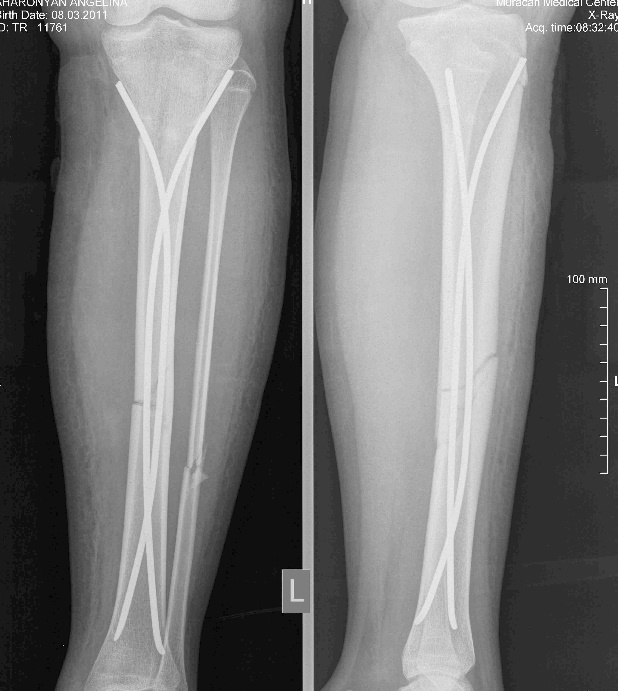

Այս ուսումնասիրությունը հիմնված է 21 հիվանդների (17 տղա, 4 աղջիկ) շարունակական խմբի բուժման արդյունքների վերլուծության վրա, որոնք ենթարկվել են տիտանե էլաստիկ մեխերով վիրահատության։ Հիվանդների տարիքը եղել է 4 տարեկանից մինչև 16 տարեկան։ 9 երեխայի մոտ կոտրվածքի պատճառ է հանդիսացել ձեռքի վրա անկումը, մնացածի մոտ կոտրվածքն առաջացել է վերջույթի ոլորման արդյունքում, վնասվածքի մեխանիզմը եղել է ուղիղ: 19 դեպքերում կոտրվածքները եղել են փակ, իսկ 2 դեպքում՝ բաց։ Ըստ վնասվածքի տեղայնացման՝ դրանք եղել են դիաֆիզար կոտրվածքներ (15 դեպք), պրոքսիմալ մետաֆիզի մակարդակի կոտրվածք (3 դեպք) և հեռավոր մետաֆիզի՝ (3 դեպք): Կոտրվածքային գծի բնույթի համաձայն՝ դիաֆիզային կոտրվածքներից հայտնաբերվել են 6 լայնակի, 4 թեք, 5 պտուտակաձև։ Մի տղայի մոտ (4 տարեկան), որի մոտ առկա էր սրունքի մ/3-ի բաց թեք կոտրվածք տեղաշարժով և մաշկի մինուս հյուսվածքներով, կատարվել է նաև վերքերի առաջնային վիրաբուժական մշակում և կարում՝ ռետինյա արտաթորիչներով։ Սակայն մի քանի շաբաթ անց սկսվել է մաշկի նեկրոզ։ Այդ իսկ կապակցությամբ կատարվել է երկրորդ վիրահատական միջամտությունը։ Կատարվել է մաշկի աուտոտրանսպլանտացիա։ Մաշկի կտորները վերցվել են առողջ ազդրի առաջային մակերեսից: (Նկ 1)

Օգտագործված մեթոդները համահունչ էին հեղինակների նկարագրած վիրաբուժական տեխնիկայի հետ: Հիմնական սկզբունքներն էին՝ ձողերի տրամագիծը, որը համապատասխանում է մեդուլյար լուսանցքի տրամագծի 30-40% -ին, ձողերի թեքությունները նույնական են, բայց հակառակ ուղղորդված և տեղակայված են կոտրվածքի մակարդակում, հարմարեցված վիրաբուժական գործիքների օգտագործումը: